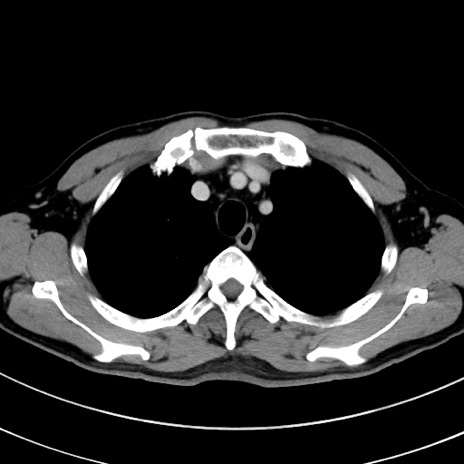

症例8(横断像)

【症例】 60歳代男性

【主訴】 黒色吐物

【現病歴】 4日前から嘔気自覚、2日前の朝食後にも嘔気あり、自分で手で嘔吐反射起こし嘔吐したところ血が混ざっていたため受診。

【既往歴】 5年前汎発性腹膜炎を伴う急性虫垂炎で手術、高血圧、前立腺肥大症、高脂血症

【身体所見】 腹部正中に手術癩痕あり 腹部平坦・軟圧痛なし膨満感あり

【データ】WBC 8400、CRP 4.54